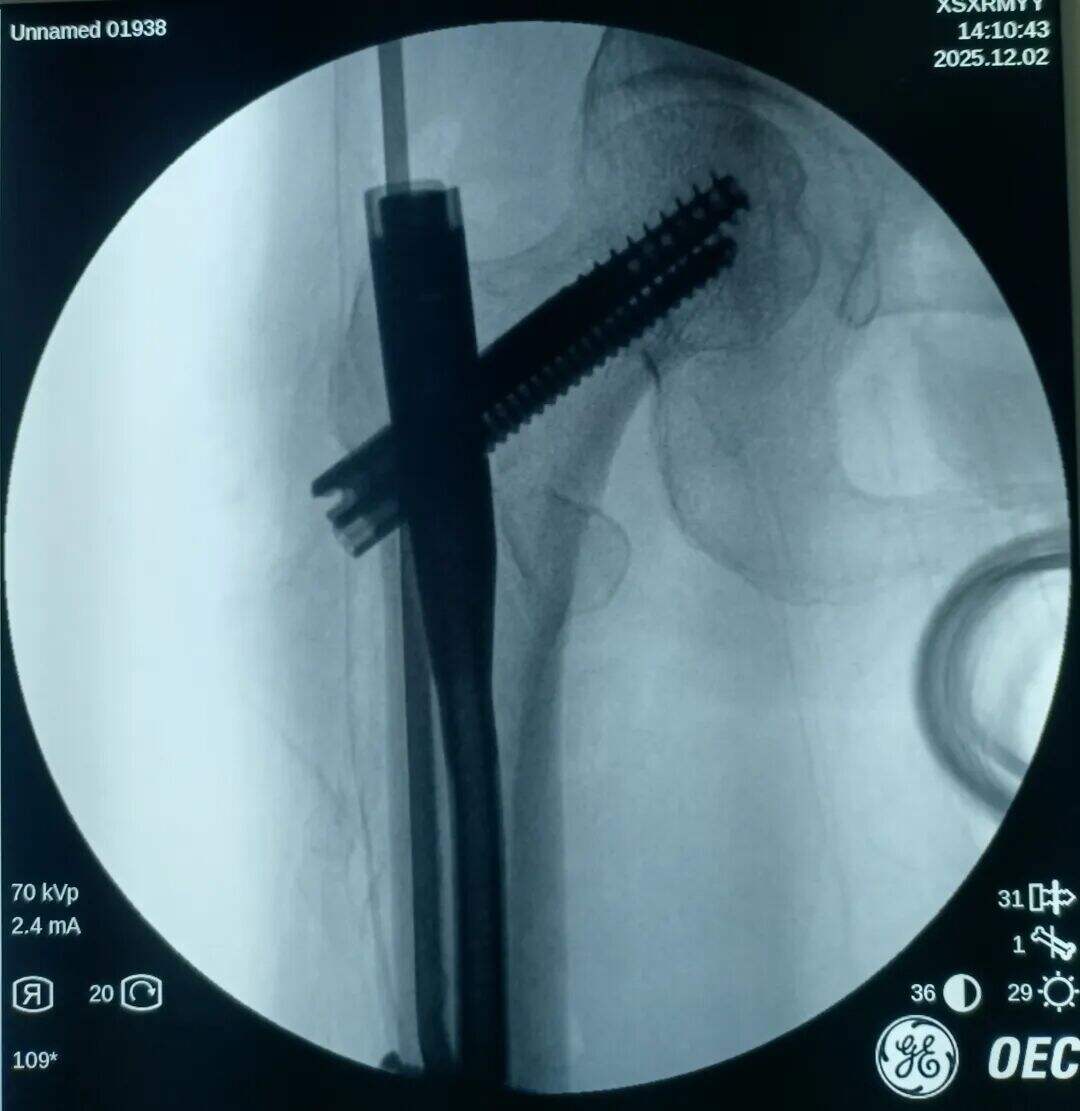

Postopek med operacijo:

Poskus zaprta zmanjšanja, vendar ni uspel. Več vlečne sile je uporabljeno, več je bilo premaknjen v višji del zaradi vlečenja iliopsoas mišice.

Narezen je bil 2 cm prednji mini-rez. Mesto zloma je bilo opazovano z prstom. Ugotovljeno je bilo, da je proksimalni fragment premaknjen navzgor, distalni fragment pa nazaj in zaklenjen. V mesto zloma je bil vstavljen klešča; pod vodstvom prsta v kombinaciji s kleščo so bili zaklenjeni fragmenti odklenjeni. Nato je bila klešča uporabljena za ohranitev kakovosti redukcije z medialno in lateralno kompresijo. Izvedena je bila običajna lokalizacija, vstavitev vodilne žice ter standardni kirurški postopek.

Medularni kanal je bil ozek. Nobenega razširjanja ni bilo izvedeno. Intramedularni klin s premerom 9 mm je bil vstavljen v tesen fit. Prilagoditev anteversije cefalomedularnega vijaka se je izkazala za težko.